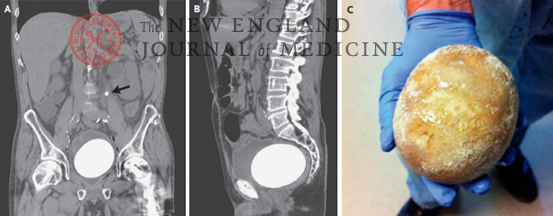

一名64岁男子因左腰部疼痛和尿潴留3天而至急诊科就诊。十余年前,他因浸润性膀胱癌接受了根治性膀胱切除术和原位小肠膀胱重建术。查体发现左腰部有压痛。腹部和盆腔计算机化断层扫描显示左输尿管近端有一个阻塞性结石(箭号),新膀胱内有一个很大的结石(图A和B)。采用肠管进行尿路改流术后,由于碳酸氢盐从尿液持续丢失、高草酸尿症以及可分解尿素的细菌在尿路中长期定植,患者容易发生尿路结石。对于储尿脏器连续的患者,例如本例患者,新膀胱中结石生成的额外风险包括尿液瘀滞、黏液产生以及膀胱再造术中使用的不可吸收手术材料。在顺行输尿管镜的辅助下,医生经皮肾造口术进入左侧输尿管,并使用激光碎石术清除了结石。患者接受了开腹新膀胱结石切除术,取出新膀胱中的结石,该结石呈鸡蛋状,大小为12 cm×9.5 cm×7.5 cm,重770 g,20%的成分为磷酸铵镁,80%为磷酸钙(图C)。患者未出现术后并发症,继续监测结石复发情况。